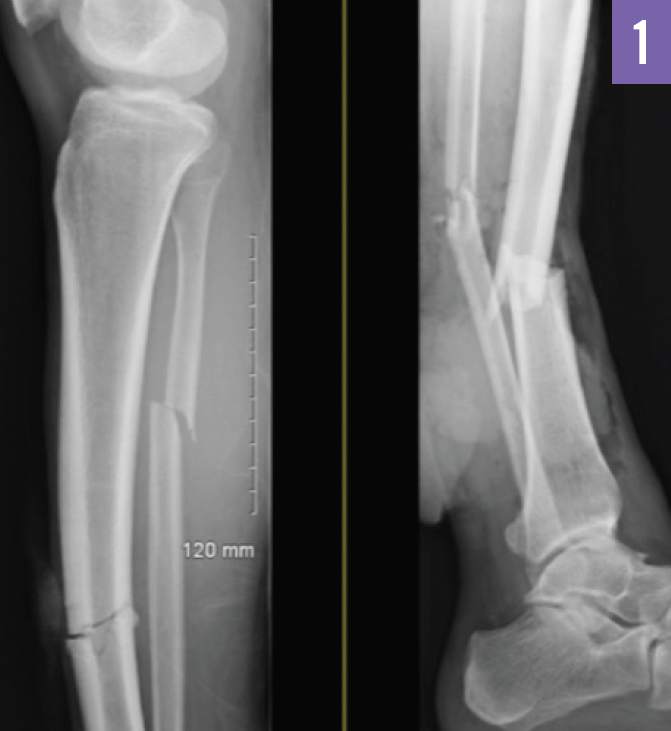

Patrick Natter, MD; Dinesh Rao, MD; Inbal Cohen-Rasen, MD; Paul L. Wasserman, DO; Dalys E. Haymes, MD; Sukhwinder Johnny S. Sandhu, MD; Austin Fischer, DO

This patient presented with findings that were suggestive of cerebral fat emboli (CFE) in fat embolism syndrome (FES).

03/15/2017